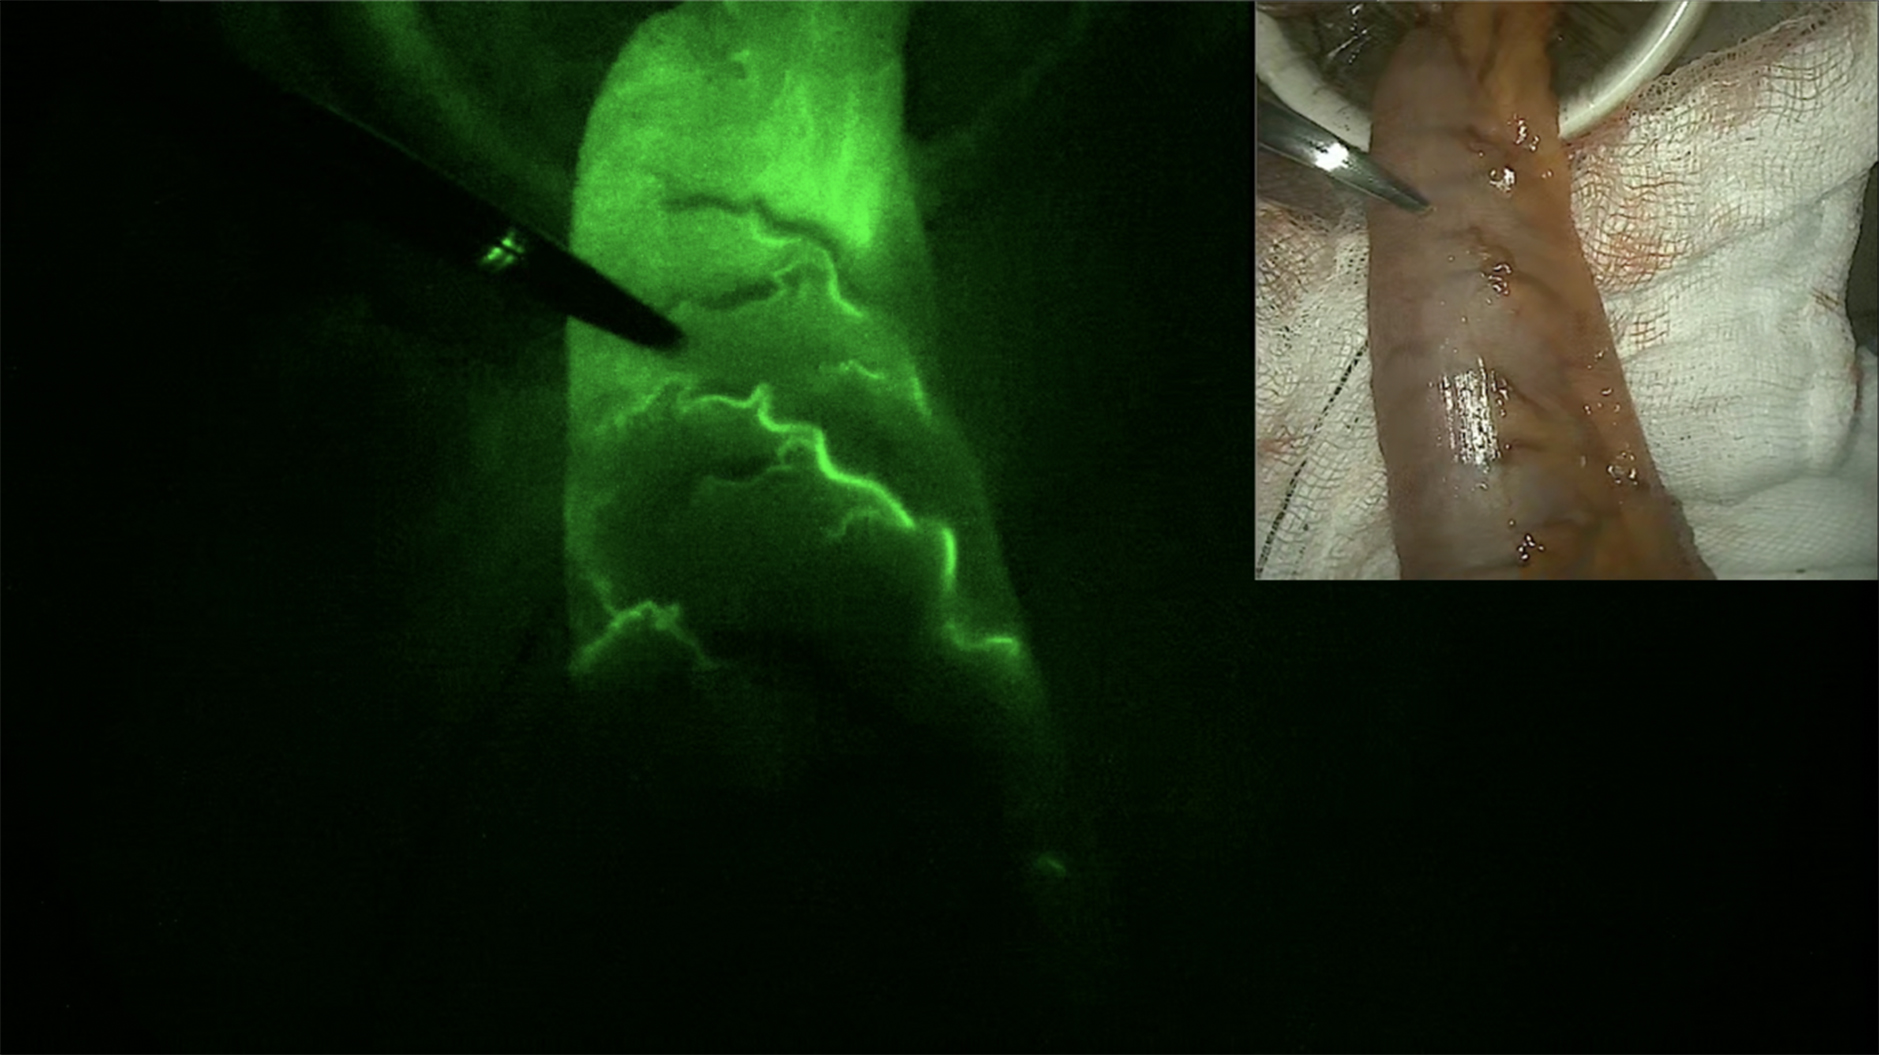

Anastomotic leak remains prevalent in colorectal surgery (CRS), resulting in significant patient morbidity and burdens on healthcare finances[4]. Key determinants of anastomotic healing include adequate blood supply to tissues and balanced microbial gut flora[5,6]. Traditional practice is to assess anastomotic bowel segments for pulsation, bleeding, and/or their colour. These are, however, subjective assessments and rarely provide a clear demarcation between well-perfused and non-perfused tissue. ICG can be used intraoperatively to provide objective perfusion assessments at the time of anastomosis [Figure 1]. The use of ICG leads to a change of resection margins in 3.7%-19% of cases compared to standard clinical assessment[7-9].

Figure 1. Indocyanine green perfusion captured using a near-infrared fluorescence camera (centre). Photograph of the same specimen in white light (top right). Original image.